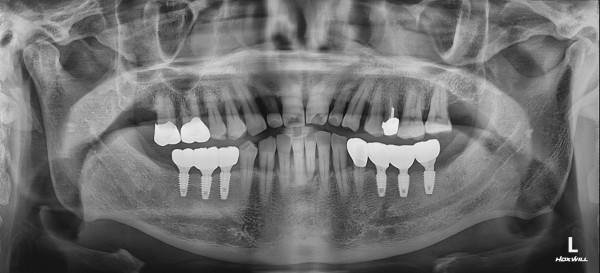

CASE 01 최고관리자 0건 25-01-06 11:58 본문 발치 후 즉시 임플란트 목록 이전글CASE 01 25.01.06 다음글CASE 01 25.01.06 댓글목록 0 댓글목록 등록된 댓글이 없습니다.